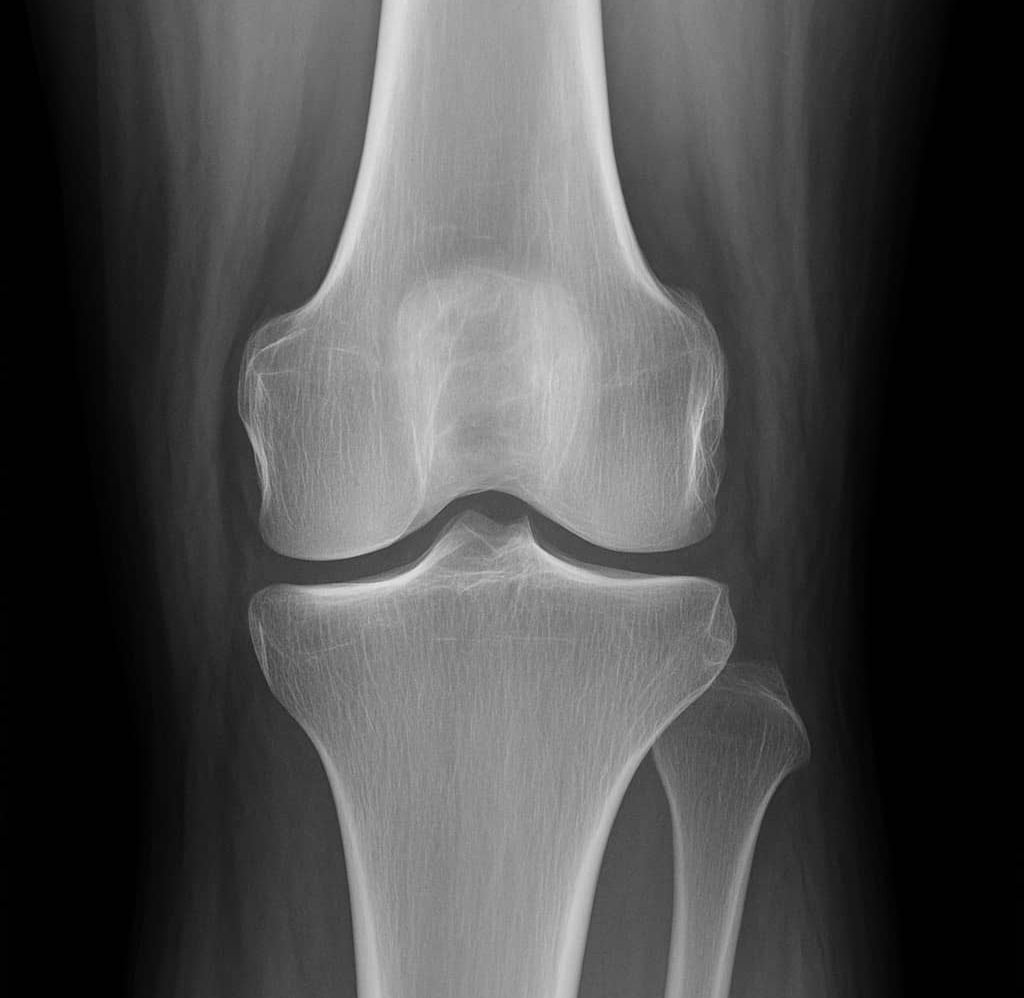

나이가 들면 무릎이나 어깨, 손목 등 관절에 통증이 찾아오며 움직임이 불편해지는 경험을 하게 됩니다. 이는 대부분 연골의 마모와 깊은 관련이 있습니다. 관절은 뼈와 뼈가 만나 움직이는 부위인데, 이때 서로 닿지 않도록 연골이라는 부드러운 조직이 완충 역할을 해줍니다. 하지만 나이가 들수록 연골이 점점 닳아 없어지고, 이로 인해 통증, 뻣뻣함, 부기 등의 증상이 나타나는 것입니다.

연골은 뼈와 뼈 사이에서 충격을 흡수하고 마찰을 줄이는 구조물로, 뮤코다당과 단백질 복합체로 구성되어 있습니다. 이 성분이 부족하면 연골이 점점 얇아지고 마모되어 관절염으로 이어질 수 있습니다. 뮤코다당・단백은 이러한 연골의 구조 유지에 필요한 물질을 공급해주는 역할을 하므로, 연골 퇴행성 변화 방지에 효과적입니다.